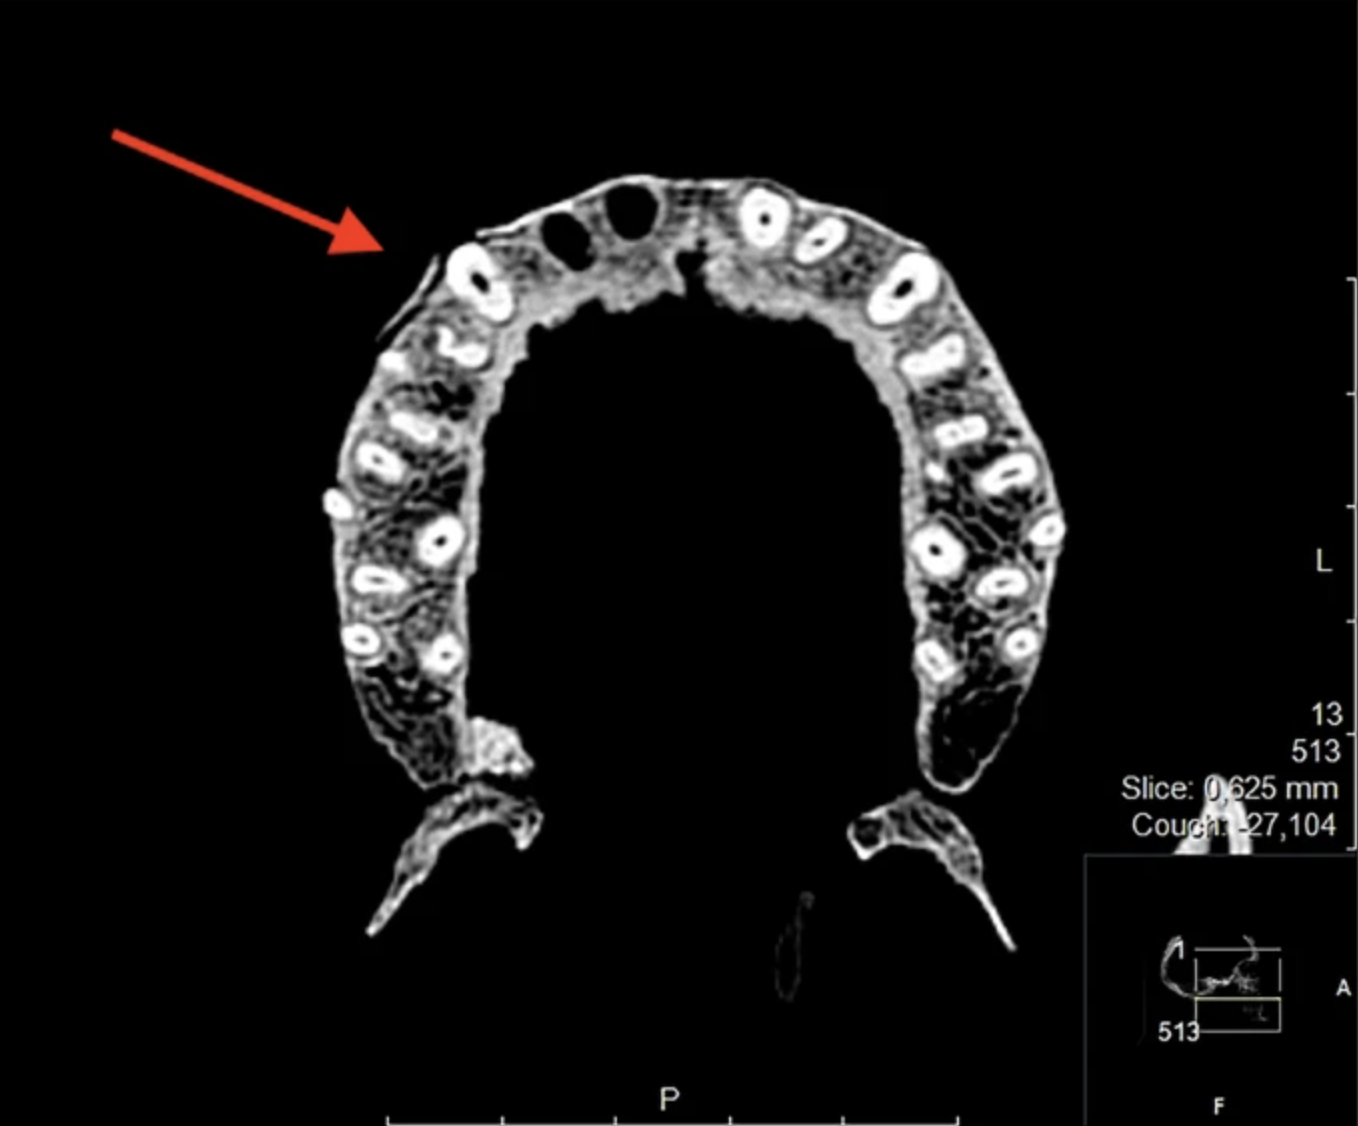

The authors of a recent study used computed tomography (CT) scans to examine 15 Viking Age skulls recovered from the Varnhem cemetery in Sweden. After consulting dentists and facial pathologists, they found that many of those ancient humans likely suffered greatly from a range of infections and other tooth-related issues.

Eighty-percent of the skulls showed evidence of a condition called apical periodontitis, a very painful infection of the tooth canal. Any access to dental care would have resulted in rudimentary and unmedicated treatment like opening a hole in the tooth to get to the pulp.